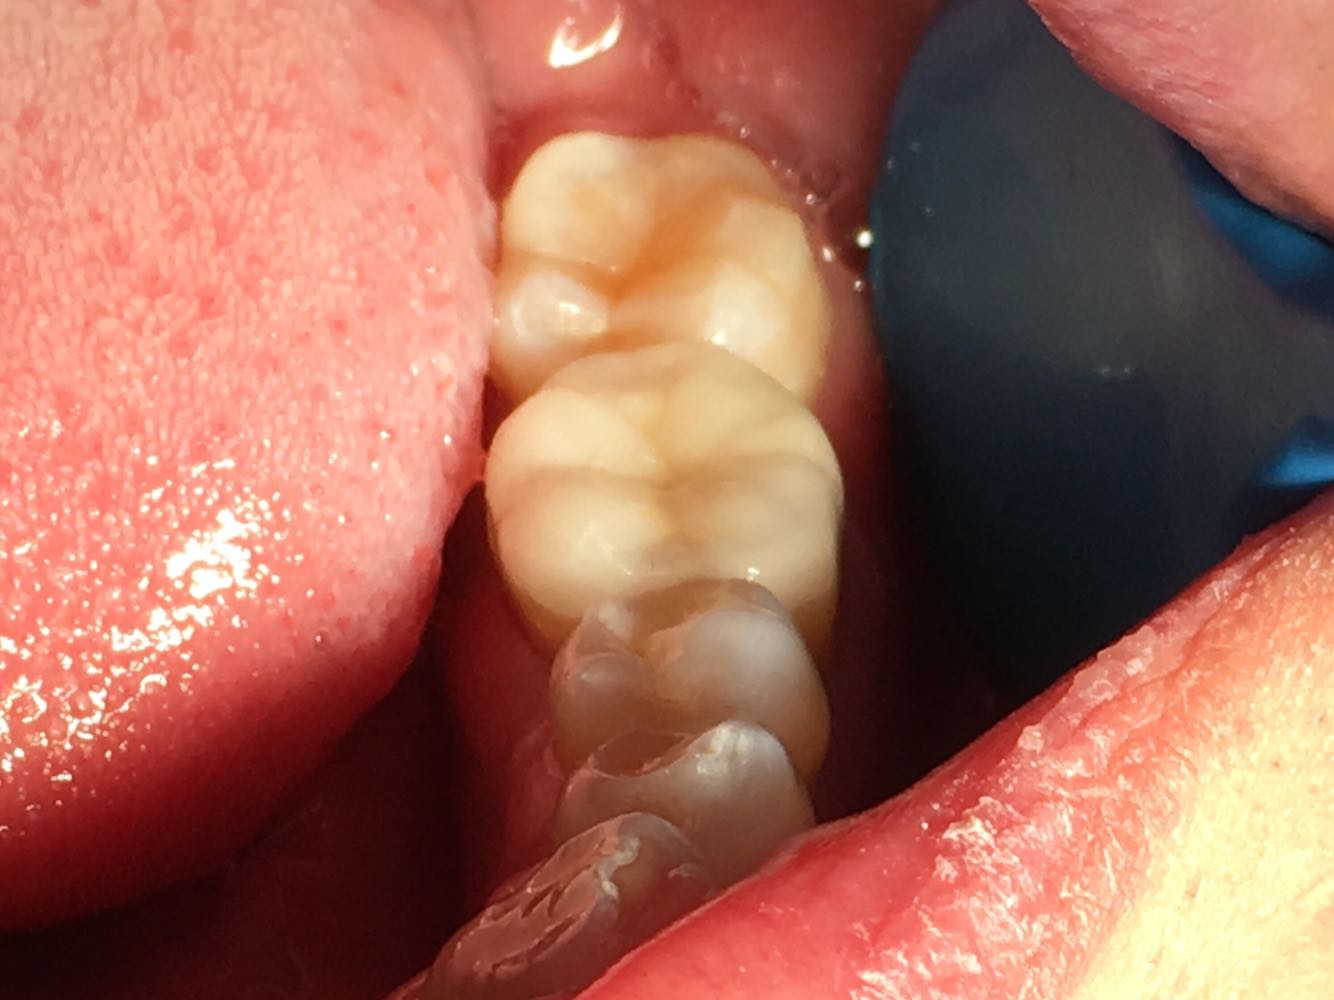

处置:左下6 去 ZOE,开髓孔无探痛,揭顶,拔髓,探及 M2D2 四根管,10#锉疏通各根管,测 WL: MB=19mm, ML=19mm, DB=18mm, DL=18.5mm, EDTA下,常规预备至F2,3%过氧化氢和0.9%生理盐水冲洗+超声荡洗根管交替进行。隔湿,干燥根管,氧化糊剂牙胶尖冷侧压充填,ZON暂封。嘱勿用患牙咬物。 2周后复诊,冷(一),叩痛(一),不松,牙龈无红肿,去除暂封物,牙体组织预备,流动树脂垫底填除倒凹,电子影像取模,送CAD/CAM制作高嵌体。 3日后复诊,嵌体配戴,调合,抛光,树脂粘接剂永久粘接。 患者对修复效果满意,交待患者使用注意事项。

随着粘结技术的发展,以前只能用全冠修复的病例,现在也可用高嵌体进行修复,牙本质也能得到很好的保存。但是,由于陶瓷的抗压强度没金属高,所以设计洞型时注意不要让应力都集中到牙本质和瓷修复体上。 全瓷修复体的制备空间设计得当,可以增加临床成活率。由于粘接技术的应用,不必为了实现机械固位而要求箱型制备,而且箱型制备还会对瓷体设计造成不利影响。以牙齿的基本解剖形态轮廓为依据进行最小厚度制备,这就要求我们选用相应直径的车针。为了确保全瓷材料的支持力,合面窝的形态修整可以省去不做。如果不遵守牙体剩余组织最小厚度要求,那么修复体失败的几率便会大大增加。如果能及早发现禁忌症以及特殊牙尖制备不当的情况,那么修复预期会更好。